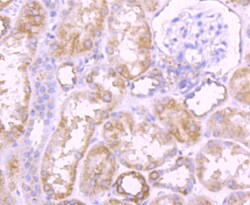

COX4 Polyclonal Antibody for Western Blot, ICC/IF, IHC (P), Flow

| Flow Cytometry, Immunohistochemistry (Paraffin), Western Blot, Immunocytochemistry | |

| Human, Mouse, Rat | |